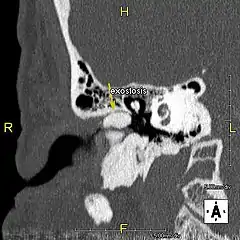

L'exostose du surfeur ou oreille de surfeur est une exostose, c'est-à-dire une croissance osseuse anormale, qui pousse vers l'intérieur du conduit auditif[1]. L'os entourant le conduit auditif réagit à l'agression thermique et mécanique de l'eau froide et de ses turbulences, par une nouvelle croissance osseuse qui a pour effet de resserrer le conduit auditif.

Du fait de la réduction du diamètre du conduit auditif, l'eau et le cérumen peuvent rester piégés entre la masse osseuse et le tympan et provoquer ainsi une infection comme une otite externe, particulièrement douloureuse.

Le contact de l’os avec le tympan peut provoquer des acouphènes[4]. Si rien n'est fait, les excroissances osseuses peuvent conduire à une obturation du conduit auditif et à une perte d'audition[1].

Le traitement de l'exostose est chirurgical, de préférence avant une obstruction avancée. L’intervention, délicate et pouvant laisser des séquelles (perte d'audition, acouphènes…)[4] s'effectue sous anesthésie générale. L'abrasion de l'os s'effectue soit par le conduit auditif soit en faisant une incision derrière le pavillon de l'oreille. La préservation de la peau interne du conduit est déterminante pour la restauration d'une couverture cutanée optimale après l'opération.